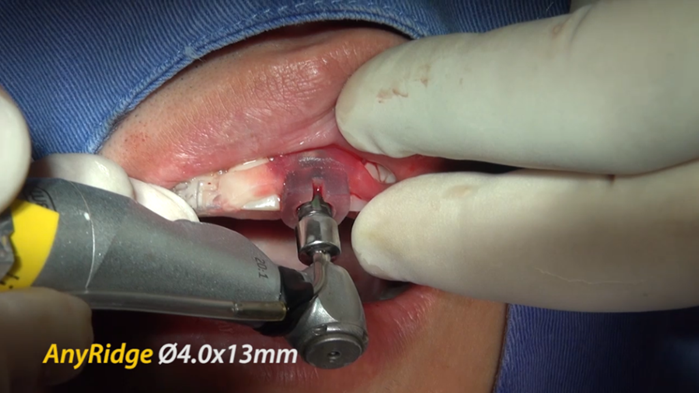

Clinical case: Extraction, immediate placement & loading using

R2GATE solution in aesthetic zone

- Courtesy of Dr. Jong-Cheol Kim, Korea-

Dr. Jong Cheol Kim, immediate loading, digital guided surgery, Digital ONE-DAY Implant, maxillary anterior, #21, guided surgery, immediate loading, AnyRidge, R2GATE, Mega ISQ, MEG Torq, R2GATE Full Surgical Kit

AnyRidge implant system, R2 Guide, R2GATE Full Surgical Kit, Mega ISQ